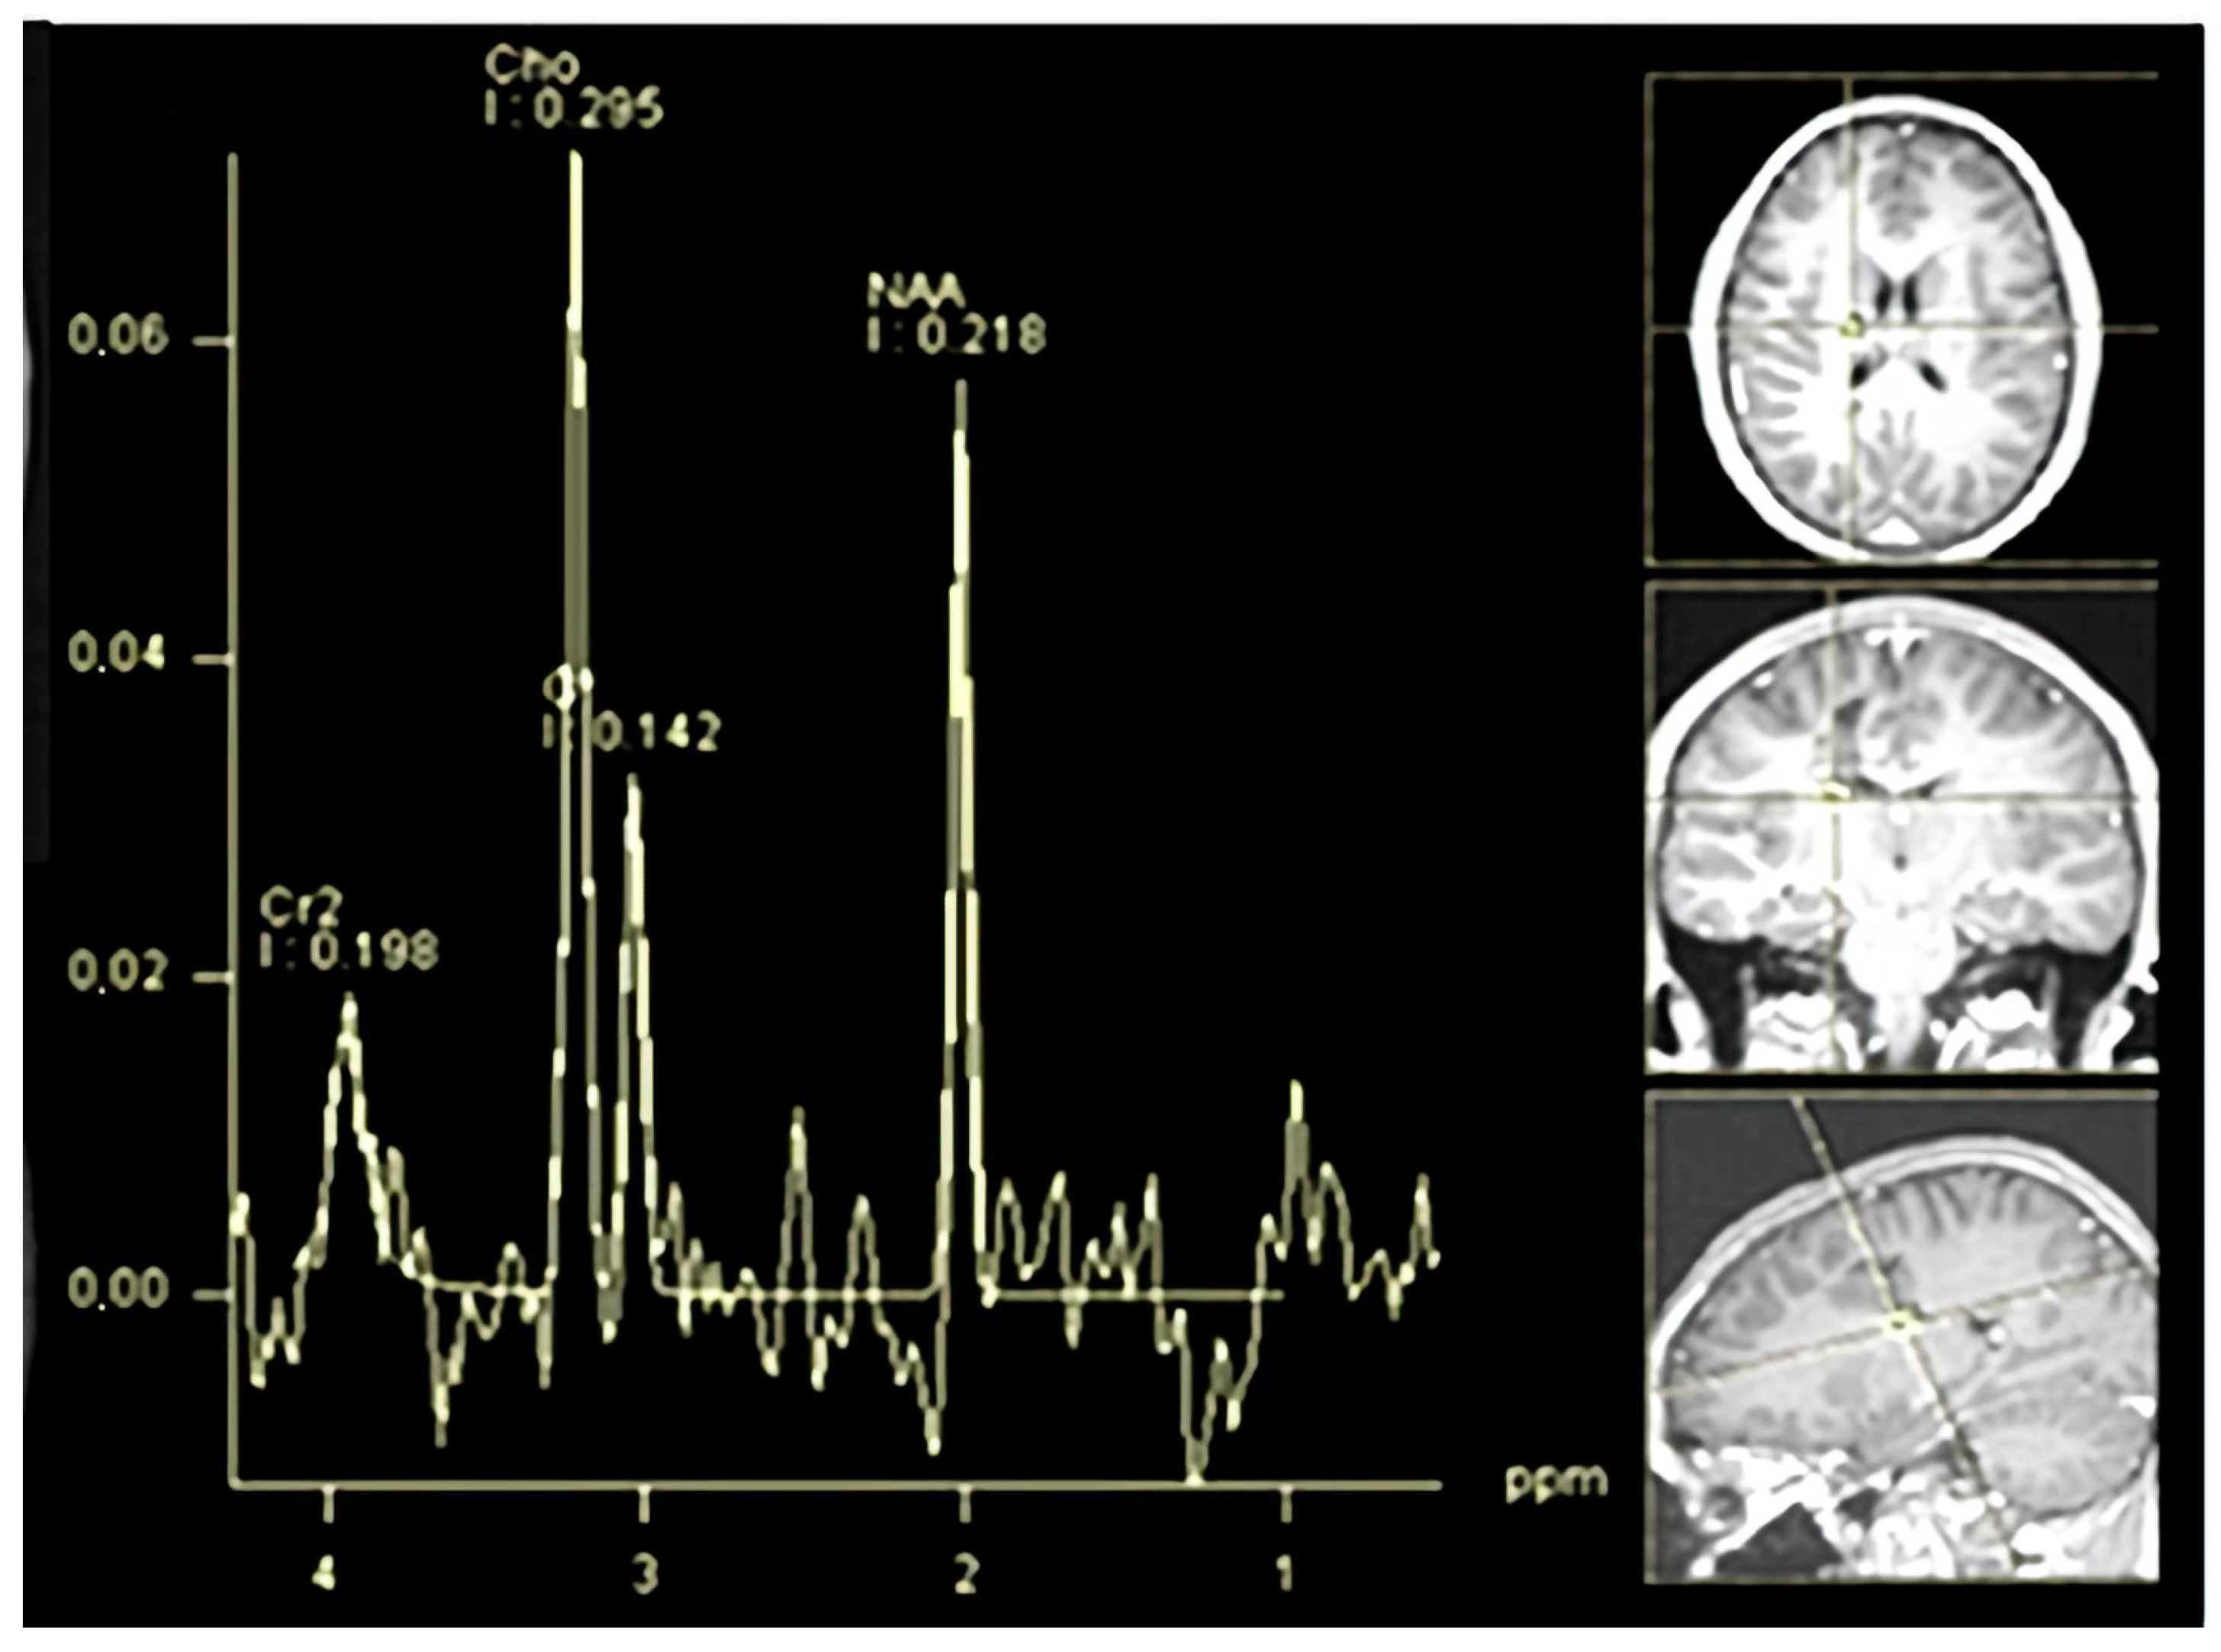

Another demyelinated region with similar features was present, and the measurement was less than one centimeter. The demyelinated area, which measured less than a centimeter, was identified as an “active plaque”. The lesion’s MR spectroscopy demonstrated a metabolic signature consistent with inflammatory demyelination instead of being a neoplastic tissue. The results can be viewed in Figure 2.

Figure 2. (AD) One month later, (A) Axial T2-weighted MRI illustrating hyperintense lesion localization. (B) Coronal FLAIR sequence confirming lesion hyperintensity and delineating precise anatomical position. (C) Sagittal FLAIR sequence highlighting the lesion’s spatial distribution and surrounding tissue involvement. (D) MR spectroscopy profile displaying decreased N-acetylaspartate (NAA)/creatine (Cr1) ratio, elevated choline (Cho)/Cr1 ratio, and lactate peaks, indicating inflammatory demyelination rather than neoplastic tissue.